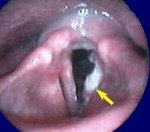

Предварительный диагноз рака гортани позволяет провести точную ларингоскопию. Выявленные эндоскопические изменения при раке гортани могут иметь самый разнообразный характер. Для эпителия голосовых связок обнаружено ограниченное образование, которое затрагивает только одну связку и выглядит как комок. В других случаях рак гортани можно определить как обычное образование с выпуклой поверхностью красноватого цвета.

Инвазивный рак гортани характеризуется утолщением голосовых связок и кровотечением во время обследования. В некоторых случаях рак гортани имеет полиповидную форму. Чтобы установить точный диагноз, полезна тренировочная биопсия, выполненная во время ларингоскопии. Если гистологическое исследование не выявляет раковых клеток и клиническая картина благоприятна для рака гортани, возможен интраоперационный диагноз.